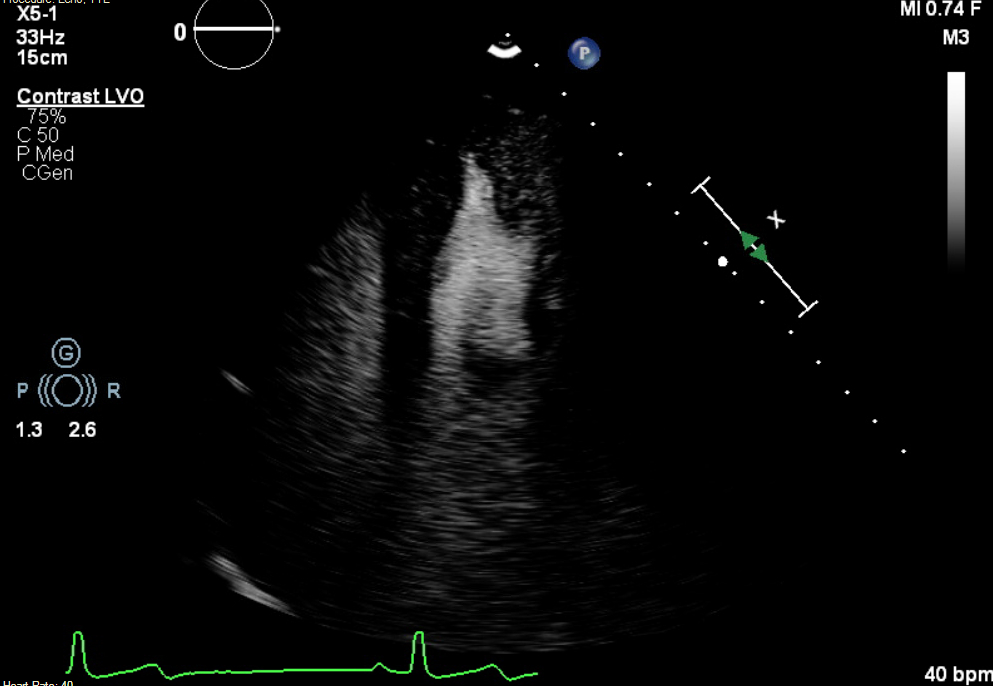

Case Presentation: A 20-year-old asymptomatic female with inferoseptal precordial T-wave inversions underwent sports pre-participation screening. Transthoracic echocardiography (TTE) revealed an apical LV crypt without hypertrophy. Cardiac MRI (CMR) demonstrated non-specific late gadolinium enhancement (LGE) in the basilar septum and inferior walls but no hypertrophy. Exercise stress testing and ambulatory monitoring were normal, and no activity restrictions were imposed. Repeat CMR at 2 years revealed new apical hypertrophy (12 mm) with apical to basal ratio of 1.2 raising suspicion for apical hypertrophy.